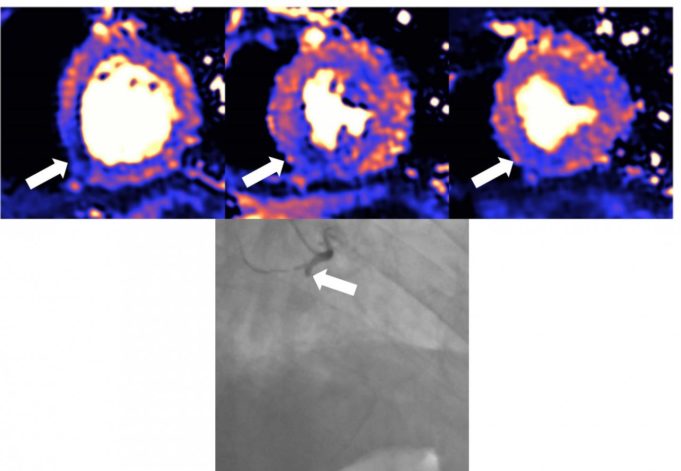

Patients identified by nuclear stress testing as having severe stress-induce...

An artificial intelligence (AI) model may be more efficient at detecting signatu...